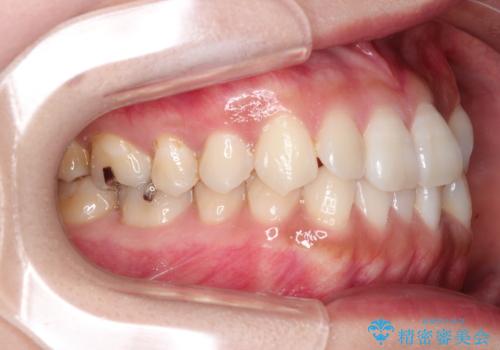

前歯のがたつきと反対咬合 インビザラインによる矯正治療

- 前歯のがたつきと反対咬合を主訴に来院されました。

下の前歯のがたつきを改善するために、右下の奥歯を後方に移動させるのと、歯と歯の間をわずかに削り、歯を並べる計画としました。

前歯の正中のずれを修正するのに少し時間がかかりましたが、整った歯並びにすることができました。